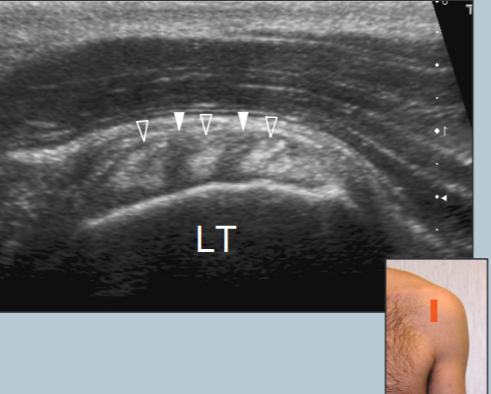

Sub-scapulaire

- Rotation externe de l’épaule, plaquée au corps

- S’insère sur le tubercule mineur

- Coupe longitudinale: on voit bien les espaces hypoechogènes entre les faisceaux du tendon

Coupe longitudinale